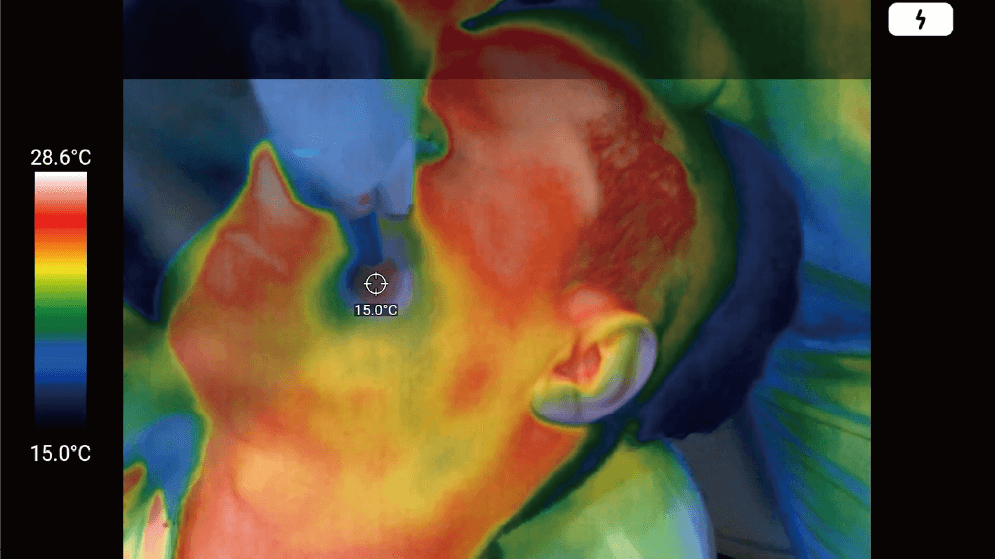

An optimal solution that enables checking the patients’ skin temperature right in front of the eye in real-time when dermatologists use heat-generating equipment such as laser or high frequency on the patients’ skin. Also, you can record and save the treatment video.

Since MetaSCOPE THERMO® accurately measures and displays changes in skin temperature in real-time, dermatologists can directly reflect changes in skin temperature during the procedure. It can recognize the highest/lowest temperature that does not cause injury leading to the maximized treatment result securing perfect patient safety. Until now, the procedure has been performed relying only on the subjective experience of the dermatologist, but now, the use of this solution can dramatically improve the procedure environment.

By wearing MetaSCOPE THERMO®, dermatologists can perform procedures while accurately checking skin temperature, increasing the accuracy of the procedure and ensuring patient safety.

Prevention of injury by detailed management

of the patients’ skin temperature

(burns, frostbite, blisters, etc.)

MetaSCOPE THERMO® guarantees the accuracy of the entire procedure, including before and after the procedure, and the accuracy of the procedure related to temperature minimizes potential side effects such as burns or frostbite that may occur on the skin due to mismanagement of the temperature.